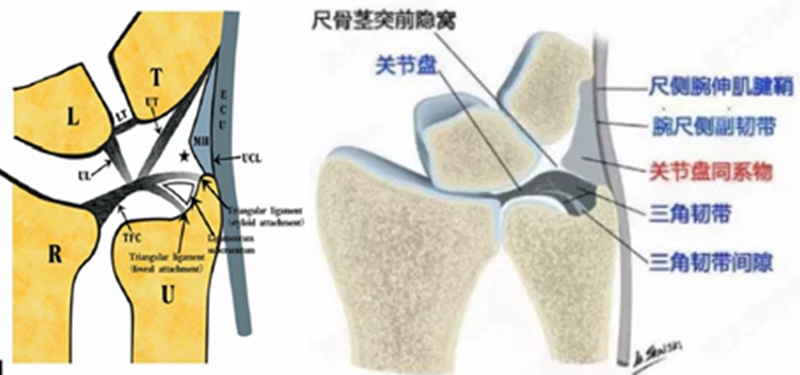

三角纤维软骨复合体(TFCC)是手腕最重要的纤维软骨-韧带复合结构,位于腕关节尺侧,分隔尺腕和远侧尺桡关节。常被称为是腕关节的“半月板”。

TFCC由以下韧带和纤维软骨组成:固有三角纤维软骨(TFC)、背侧桡尺韧带(DRUL)、掌侧尺韧带(PRUL)、尺三角韧带(UTL)、尺月韧带(ULL)、月三角韧带(LTL)、尺侧腕伸肌腱(ECU)鞘、尺侧副韧带(UCL)及半月板类似体(MH)。

血供

TFCC的周边约20%的区域(桡侧缘除外)有血供,中心约80%的区域无血供。这就决定了TFCC不同部位损伤后具有完全不同的愈合能力,同时也提示不同的分型需采取不同的治疗方式。早期明确损伤的性质以及撕裂的部位对临床治疗方法的选择具有关键性指导意义。